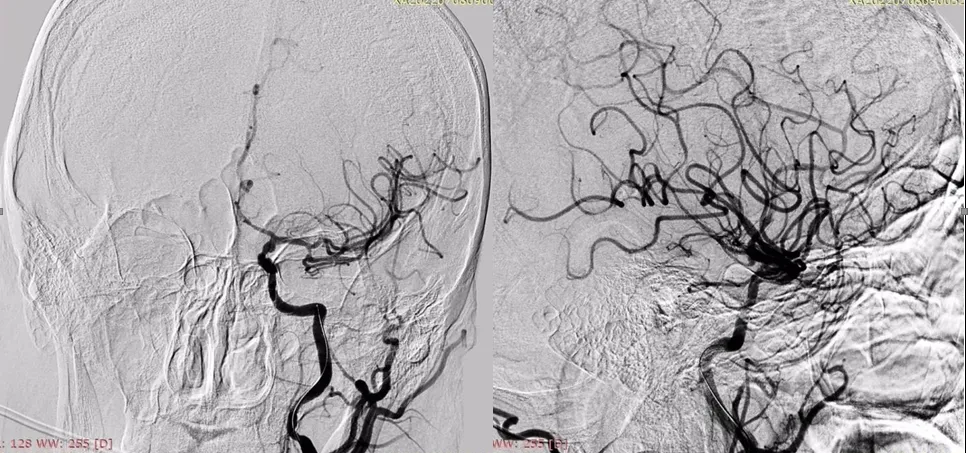

Рисунок 2. Результати МСКТ-ангіографії церебральних судин.

Результати МСКТ-ангіографії (ліворуч коронарна, праворуч – аксіальна MIP-реконструкція) свідчили про оклюзію лівої внутрішньої сонної артерії (ВСА) в екстракраніальному сегменті

(жовта стрілка) та оклюзію лівої середньої мозкової артерії (СМА) в сегменті М1 (червоні стрілки).